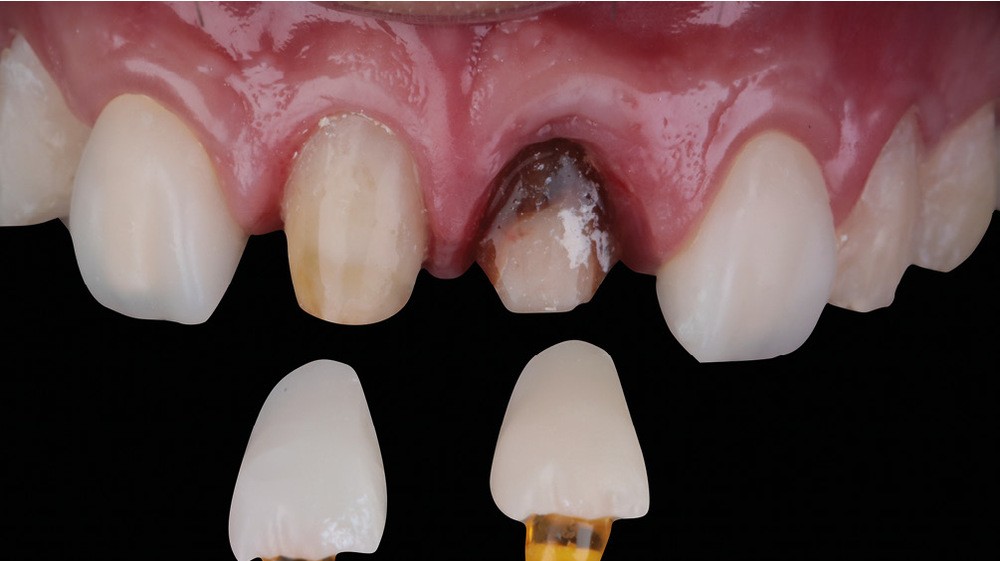

Acte 4 : préparation dentaire et gestion du rose additive (fig. 5 et 6)

À trois mois, les tissus en cours de cicatrisation se stabilisent ; nous passons à la préparation des dents [3].

Au vu des larges plages de cément exposées, nous optons pour une préparation de type couronne sur 53, 11, 21 et 23, afin de privilégier un assemblage prothétique de type scellement. Pour 15, 14, 24 et 25, nous resterons essentiellement dans l’émail et en vestibulaire. Ce choix nous oriente sur une préparation de type facette dont l’assemblage prothétique se fera par collage.

Nous observons que les tissus mous autour de la dent dyschromiée 21 se sont affinés et laissent transparaître le substrat radiculaire [4]. Un épaississement des tissus mous à l’aide d’une greffe de conjonctif s’impose. Dernières retouches également pour la ligne des collets par de petites gingivectomies au bistouri électrique. Des couronnes provisoires, basées sur le nouveau profil d’émergence, sont ensuite posées afin d’obtenir une cicatrisation guidée.